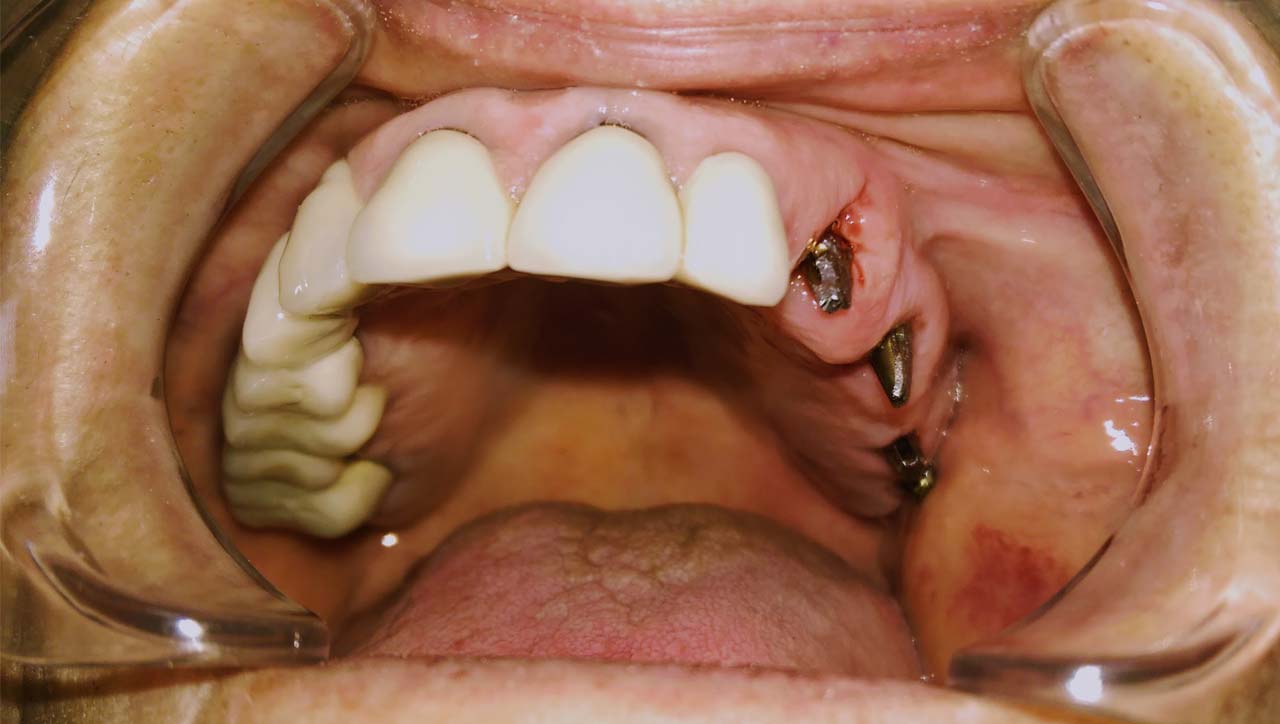

A mozgó, törött fogakon álló hidat a fogakkal együtt eltávolítottuk.

A fogak helyére, és a stratégiailag jó csontállományú hátsó területre azonnal behelyezett implantátumokra 3 nap múlva elkészítettük az esztétikus, azonnal terhelhető ideiglenes hidat.